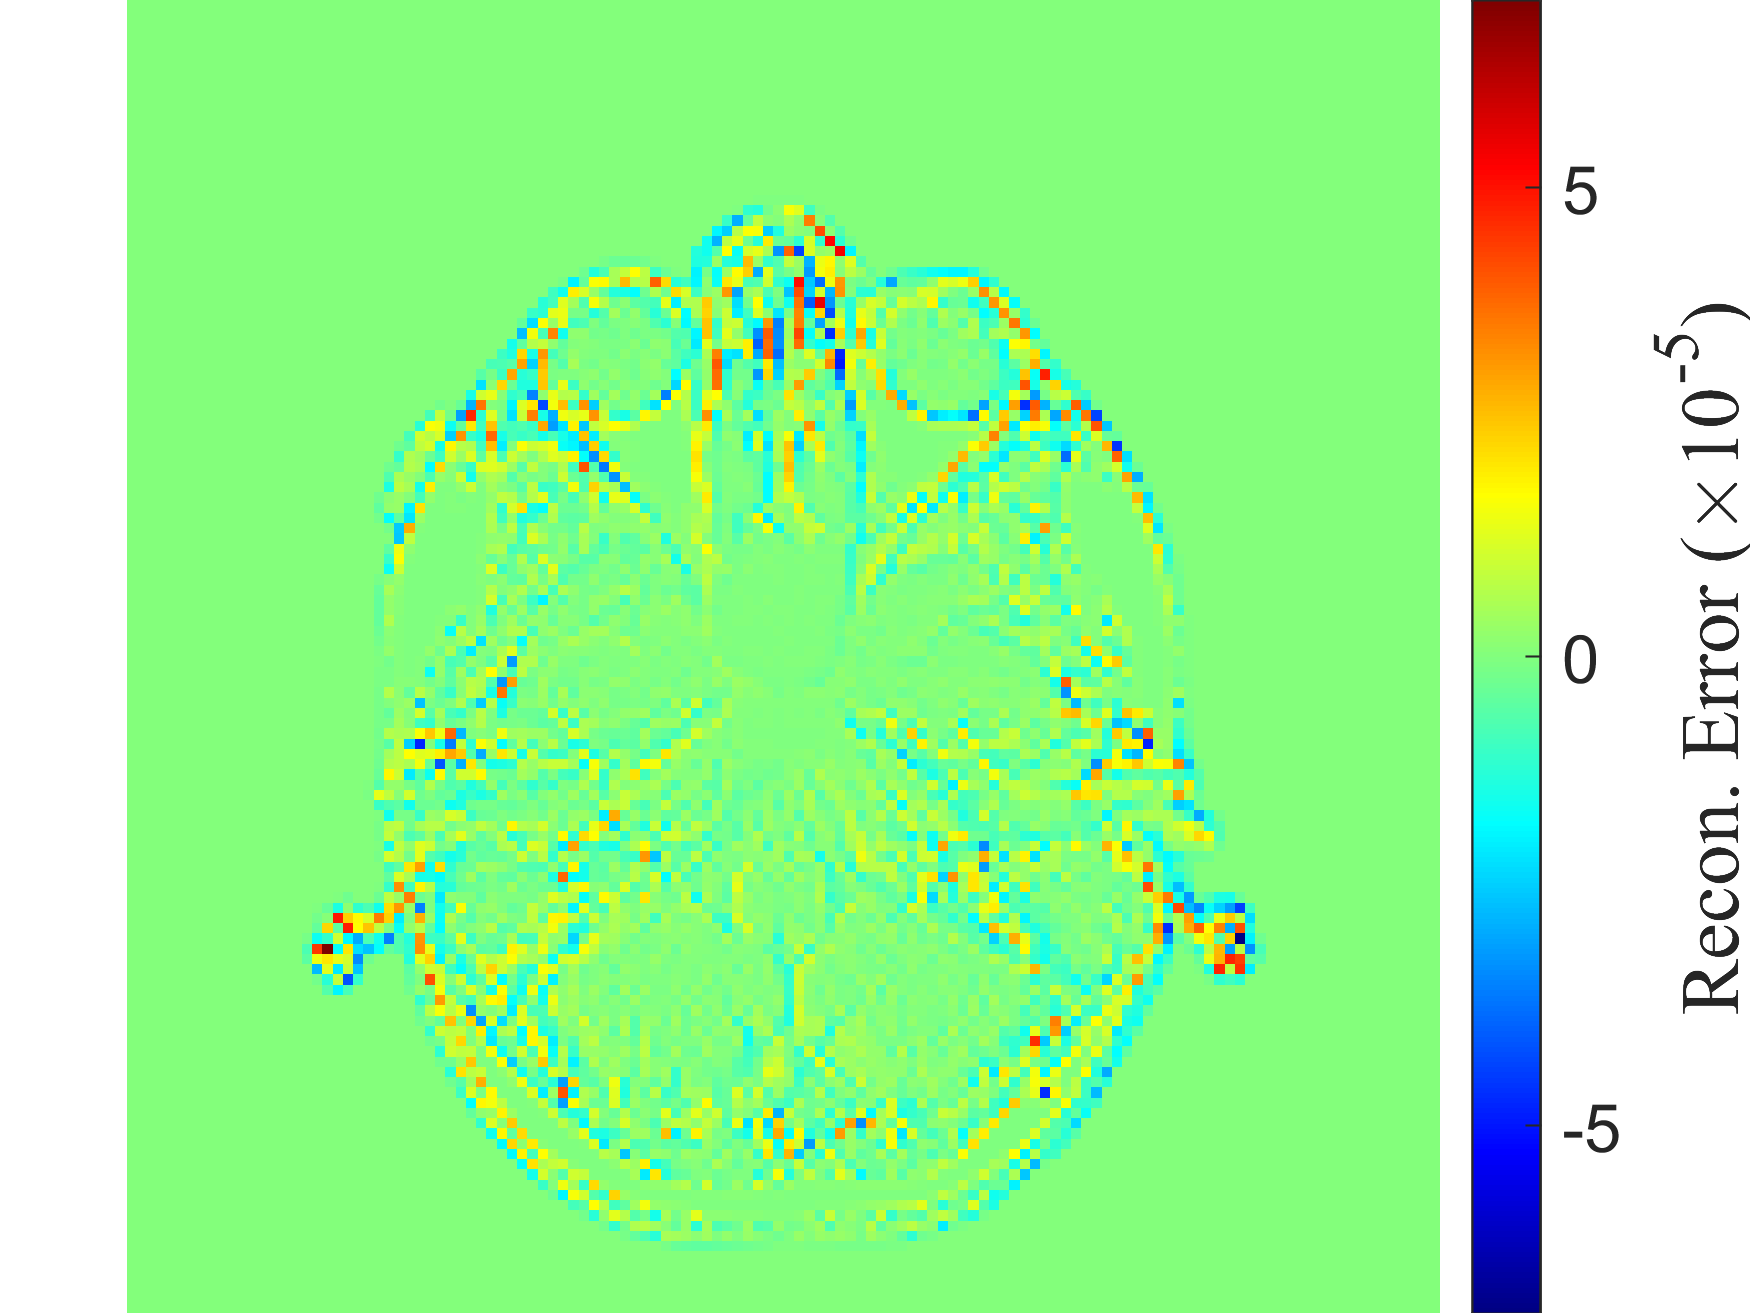

Refer to caption

(h) DDM

(i) Original density profile

(j) kk-NN

Figure I.3: Representative original and reconstructed density profiles for the Hughes 2D pedestrian model dataset (M=200×50M=200\times 50). Left column panels show the original density profile, while panels 3(b), 3(d), 3(f), 3(h) and 3(j) show its reconstructions, obtained with the five decoders: RANDSMAP-RFF with P=NP=N, RANDSMAP-MS-RFF with P=NP=N, RANDSMAP-Sig with P=NP=N, DDM and kk-NN, respectively. For the RANDSMAP decoders, the displayed configuration is the one achieving the lowest training error among all variants of that type (see full comparison in Fig. 4(a)).